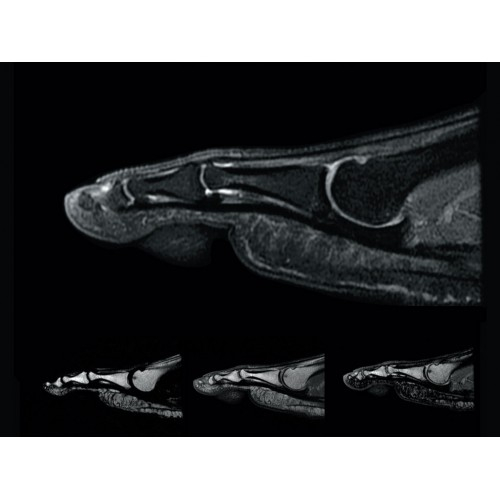

МР-томограф Optima MR450w позволяет получать изображения исключительно высокого качества, которые помогают установить диагноз. Чтобы удовлетворить ожидания клиентов в отношении высокого качества, в МР-томографе Optima MR450w были сохранены дополнительные возможности платформы Discoverу, привнесшие в его работу универсальность и мощь.

• РЧ-катушки, оптимизированные для исследования конкретных участков тела — элементы катушек высокой плотности располагаются вокруг исследуемых участков тела и при необходимости обеспечивают расширенный охват и оптимальное качество изображений при каждой процедуре.

• Широкое поле зрения — поле зрения шириной 50 см позволяет охватывать крупные анатомические области за меньшее число сканов.